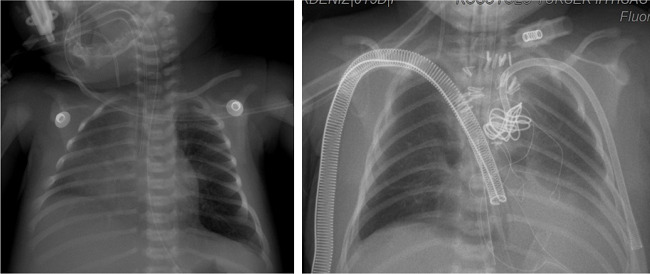

An intubated newborn with hypoplastic left heart syndrome was admitted to our clinic from another center. The patient’s COVID-19 RT-PCR test was found to be negative, and no pneumonia findings were identified in the Pa chest X-ray and CT, but the mother’s COVID-19 RT-PCR test was found to be positive (Figure 3). Norwood stage 1 operation was performed on the patient. The control COVID-19 RT-PCR test in the postoperative period was also found to be negative. The patient was monitored on ECMO with intubation for 23 days in the ICU. The patient, whose general condition deteriorated during follow-up, died due to sepsis caused by a non-coronavirus cardiac infection.